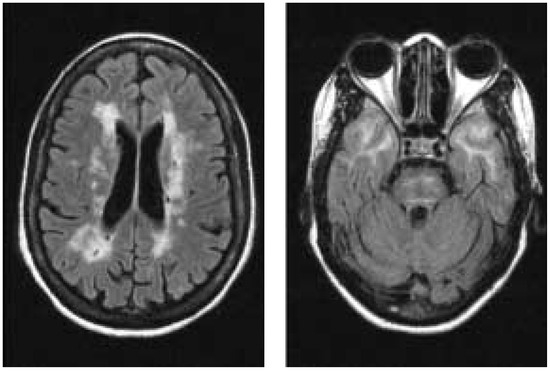

Review

Neuroimaging of the ischaemic penumbra

by Karl-Olof Lövblad

As ischaemic stroke is no longer considered a fatal or catastrophic disease with no or little therapeutic possibilities, it is indispensable to demonstrate the target for any intervention. This target is the ischaemic penumbra, which is considered to be tissue at risk of [...] Read more.

As ischaemic stroke is no longer considered a fatal or catastrophic disease with no or little therapeutic possibilities, it is indispensable to demonstrate the target for any intervention. This target is the ischaemic penumbra, which is considered to be tissue at risk of undergoing infarction if nothing is done acutely within the time window. This penumbra has varied in its definition over the last few decades but now an operational model based on new magnetic resonance imaging or computed tomography techniques has emerged. The proposed model is the diffusion-perfusion mismatch, where the central diffusion lesion represents the infarcted core which is surrounded by an area of diminished perfusion.This model shows progression of the DWI lesion into the periinfarct hypoperfusion and is reversed in case of successful intervention such as thrombolysis. Full article